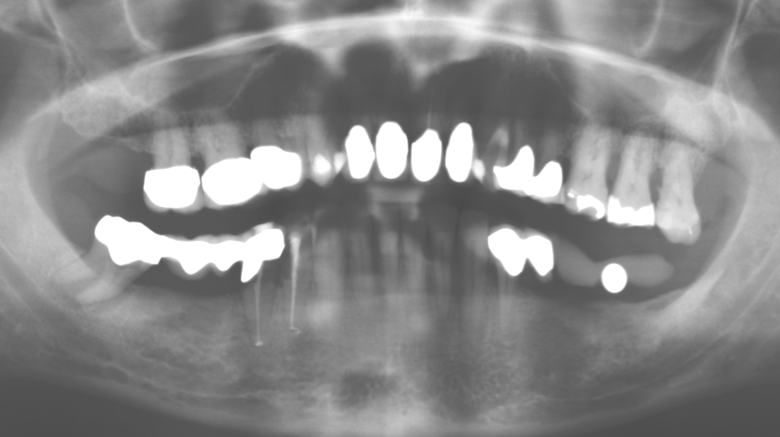

Standardised and regular risk-adapted care in the scope of SPT is the key to treatment success for the clinical long-term success in periodontically compromised patients. This is particularly true for patients fitted with implants following successfully completed periodontal treatment (Fig. 11a and b).